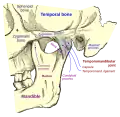

Vista lateral do crânio.

Vista lateral do crânio. Crânio visto de frente.

Crânio visto de frente. Close-up.

Close-up. Vista lateral do crânio.

Vista lateral do crânio. Esquerda fossa infratemporal.

Esquerda fossa infratemporal. Corte sagital do crânio.

Corte sagital do crânio. Articulação da mandíbula. Aspecto lateral.

Articulação da mandíbula. Aspecto lateral. Base do crânio. Superfície superior.